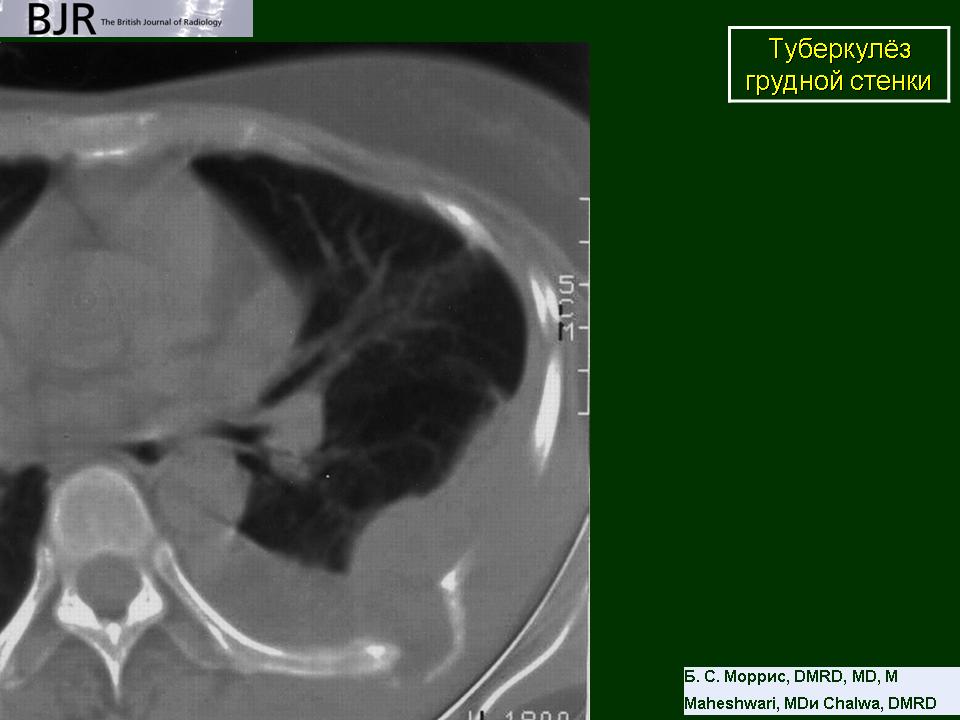

Туберкулёз грудной стенки. Ср, 13/12/2017 - 21:33 #1 Катенёв Валенти... Не на сайте Был на сайте: 7 лет 6 месяцев назад Зарегистрирован: 22.03.2008 - 22:15 Публикации: 54876 Рисунок 21.17 Туберкулезный остеомиелит с участием грудины

Рисунок 21.17